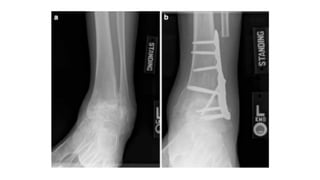

After ankle fusion with an anterior fusion plate

and locking screws.